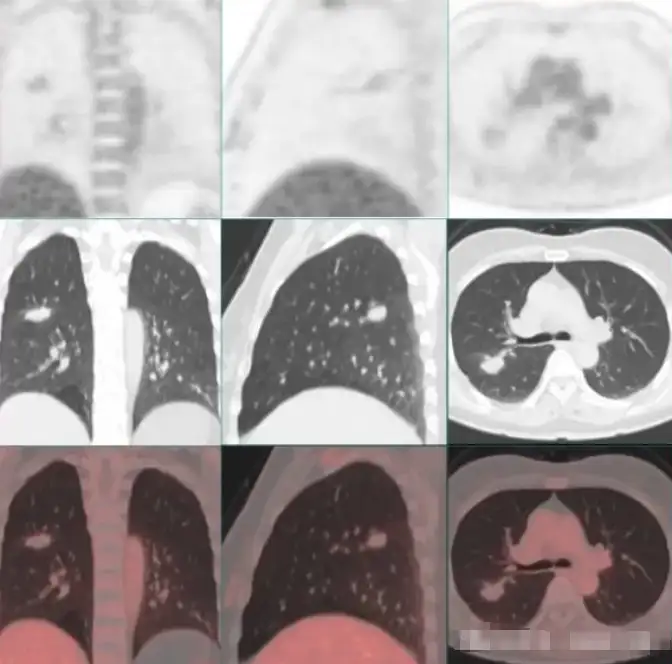

PET/CT图像显示右肺上叶后段可见团状软组织密度结节,边缘呈浅分叶,可见毛刺、胸膜牵拉及血管集束,大小约26mm×21mm×14mm(长×宽×高),伴FDG摄取轻度增高,SUVmax 1.7如上图所示,病灶与局部斜裂胸膜粘连,似有跨叶间裂累及右肺下叶趋势。纵隔及双侧肺门未见异常淋巴结显示,扫描野内其他区域亦未见明显异常结构改变或异常FDG摄取。

检查意见:右肺上叶FDG代谢轻度增高软组织肿物,不除外恶性病变,建议组织病理学检查。[病例来源于北京大学国际医院]